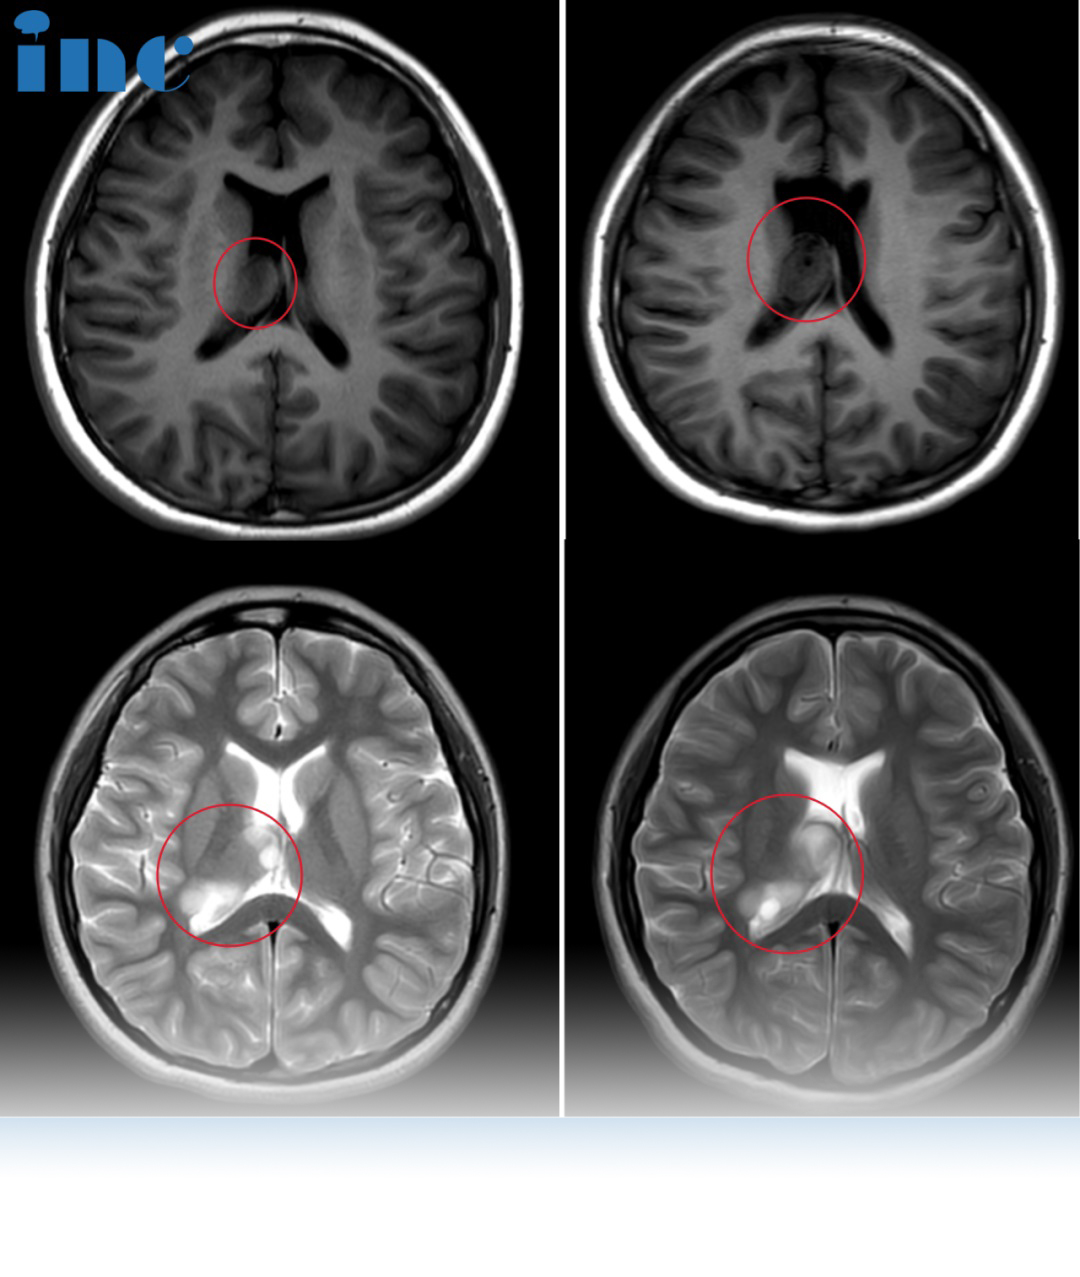

孩子生了病,当家长的比谁都着急,就算是是拼尽,都想着替孩子把病治好。诊室迎来新的患者,一位13岁脑瘤患儿小樱的母亲。在此之前为了评估患儿的情况,巴教授已经看过小樱的视频以及病历资料。“我研究了现在的影像和之前的影像对比,肿瘤已经变大了,从现在这个情况看,我认为是可以进行手术。”21年5月巴教授来华期间,小樱父母就选择与巴教授进行面对面咨询,当时肿瘤还没有进展,因此没有选择手术。但这一次再次对比影像,没想到病情进展了……

巴教授:肿瘤以一种弯曲不同的方式在侧脑室中生长。保守并不是个好主意,因为肿瘤会继续生长。手术并不紧急,但是这个孩子为什么要等待呢?如果她现在没有症状,这是较好的机会。如果她出现了症状,那么肿瘤已经到了晚期,那就很糟糕了。

巴教授:我经常做这类手术,我可以操作这个。切除率至少90%。如果可以的话,我可以尝试将肿瘤完全切除,但现在我还不能确定,因为肿瘤的形状太奇怪了。